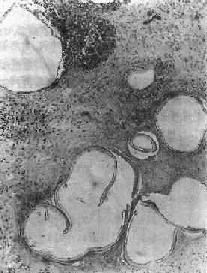

包虫囊壁分为内、外两层,内层为生发层,厚约22~25μm,由单层或多层的生发细胞构成,具有显著的繁殖能力。生发层细胞向内芽生,可在囊内壁形成无数小突起,渐变成单层小囊泡,即生发囊(图19-18)。生发囊脱落,即变子囊,其内壁又可生出5~30个原头蚴。子囊结构与母囊相同,还可再产生生发囊或孙囊。在较老的包虫囊内,子囊可多达数百个。生发层偶也向外芽生形成外生囊。

图19-18 包虫囊肿

囊壁外层为角皮层,内为生发层,并有生发囊形成,其内可见多数原头蚴